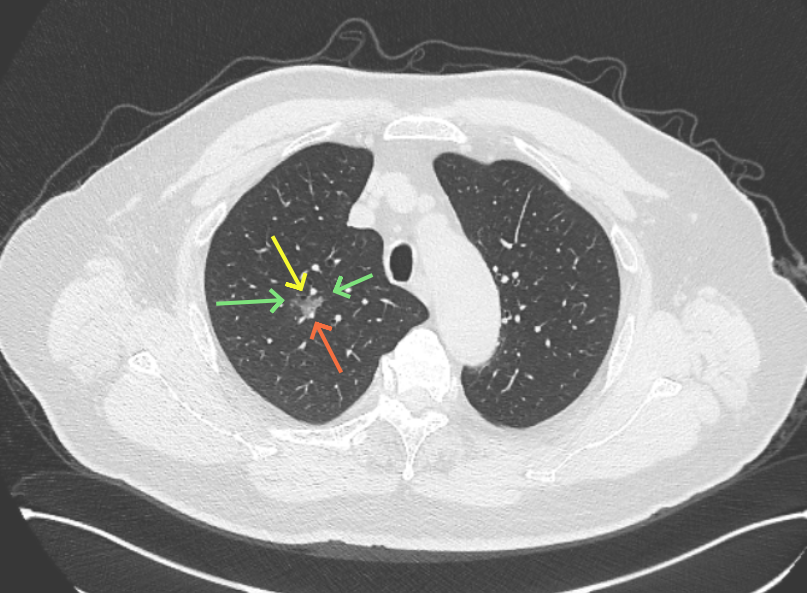

方形的是25年的,红色的主病灶,磨玻璃密度伴少许略偏高点密度,但还说不上典型混合磨玻璃病灶,考虑原位癌或微浸润性腺癌可能性大;蓝色的轮廓与边界欠清,位置靠上叶中央,无法段切或楔切;黄色的多发均淡而纯,分布在两肺。圆形粉色的是主要的两处23年时的样子,对比说不上很明显进展。鉴于若手术得切肺叶,何况两肺他处仍的结节,年纪又74了。我倾向保守点,先6-9个月复查,等进展并风险增加再来考虑怎么办的事。意见供参考!

影像展示与分析:

病灶B似乎灶内有少许密度略偏高,但瘤肺边界欠清晰,总体说不上太显著的进展。

当时结友自己还觉得有点实性成分,血管感觉也有增粗。而我觉得整体密度仍是磨玻璃,轻微的变化仍不足以影响临床决策的程度。

病灶没有确切纵隔窗可见的实性成分,但与血管关系较为密切。